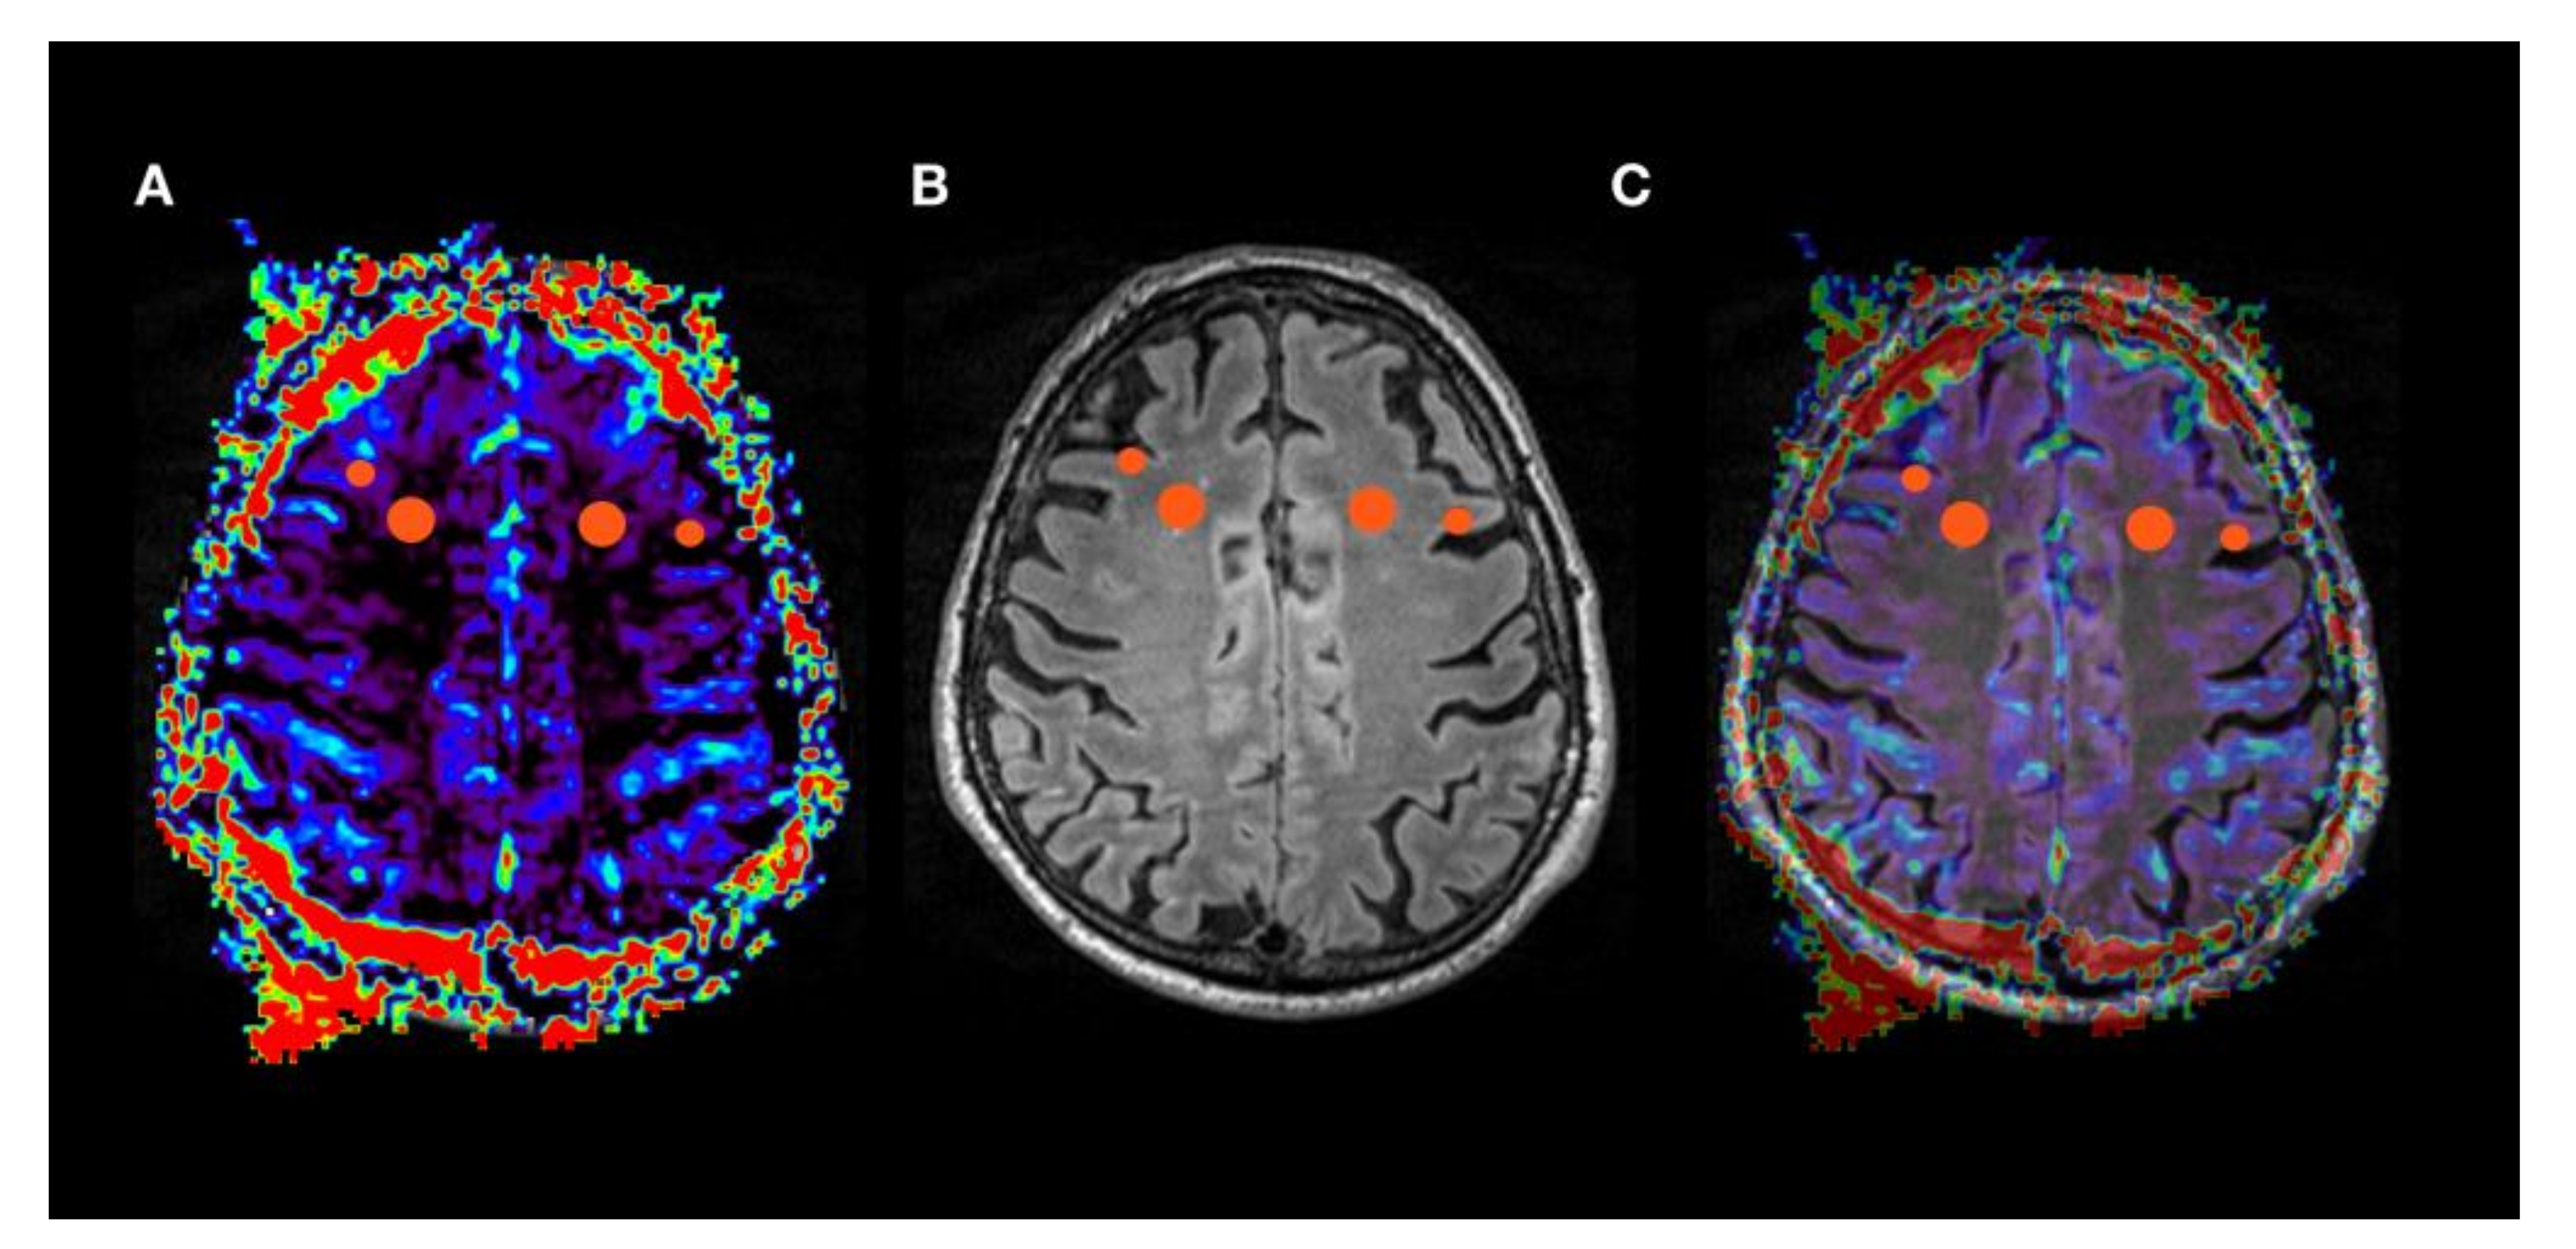

| MNI Cortex | MNI White Matter | |||||

|---|---|---|---|---|---|---|

| X | Y | Z | X | Y | Z | |

| left frontal | −36 | 2 | 53 | −12 | 7 | 51 |

| left parietal | −28 | −68 | 41 | −19 | −53 | 41 |

| left temporal | −53 | −7 | −22 | −42 | −1 | −22 |

| right frontal | 24 | 11 | 53 | 17 | 6 | 53 |

| right parietal | 28 | −68 | 41 | 19 | −53 | 41 |

| right temporal | 53 | −7 | −22 | 42 | −1 | −22 |